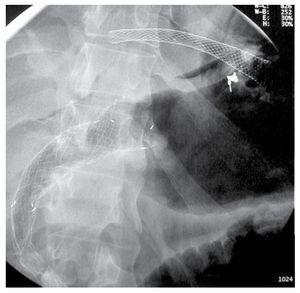

¿ Figure 1. With the linear array echoendoscope located in the stomach, the left bile duct was targeted and an antegrade cholangiography was performed, showing diffuse bile duct dilation that reached the distal common bile duct. A guide wire was inserted through the needle into the bile duct, and manipulated until we managed to get through the distal common bile duct stenosis, papilla and duodenal stent into the duodenal lumen. We extracted both ends of the guide wire with a rendezvous technique, and when the frontal view endoscope was inserted over the transgastric end of the wire, the gastric perforation was clearly shown with obvious pneumoperitoneum (arrow).